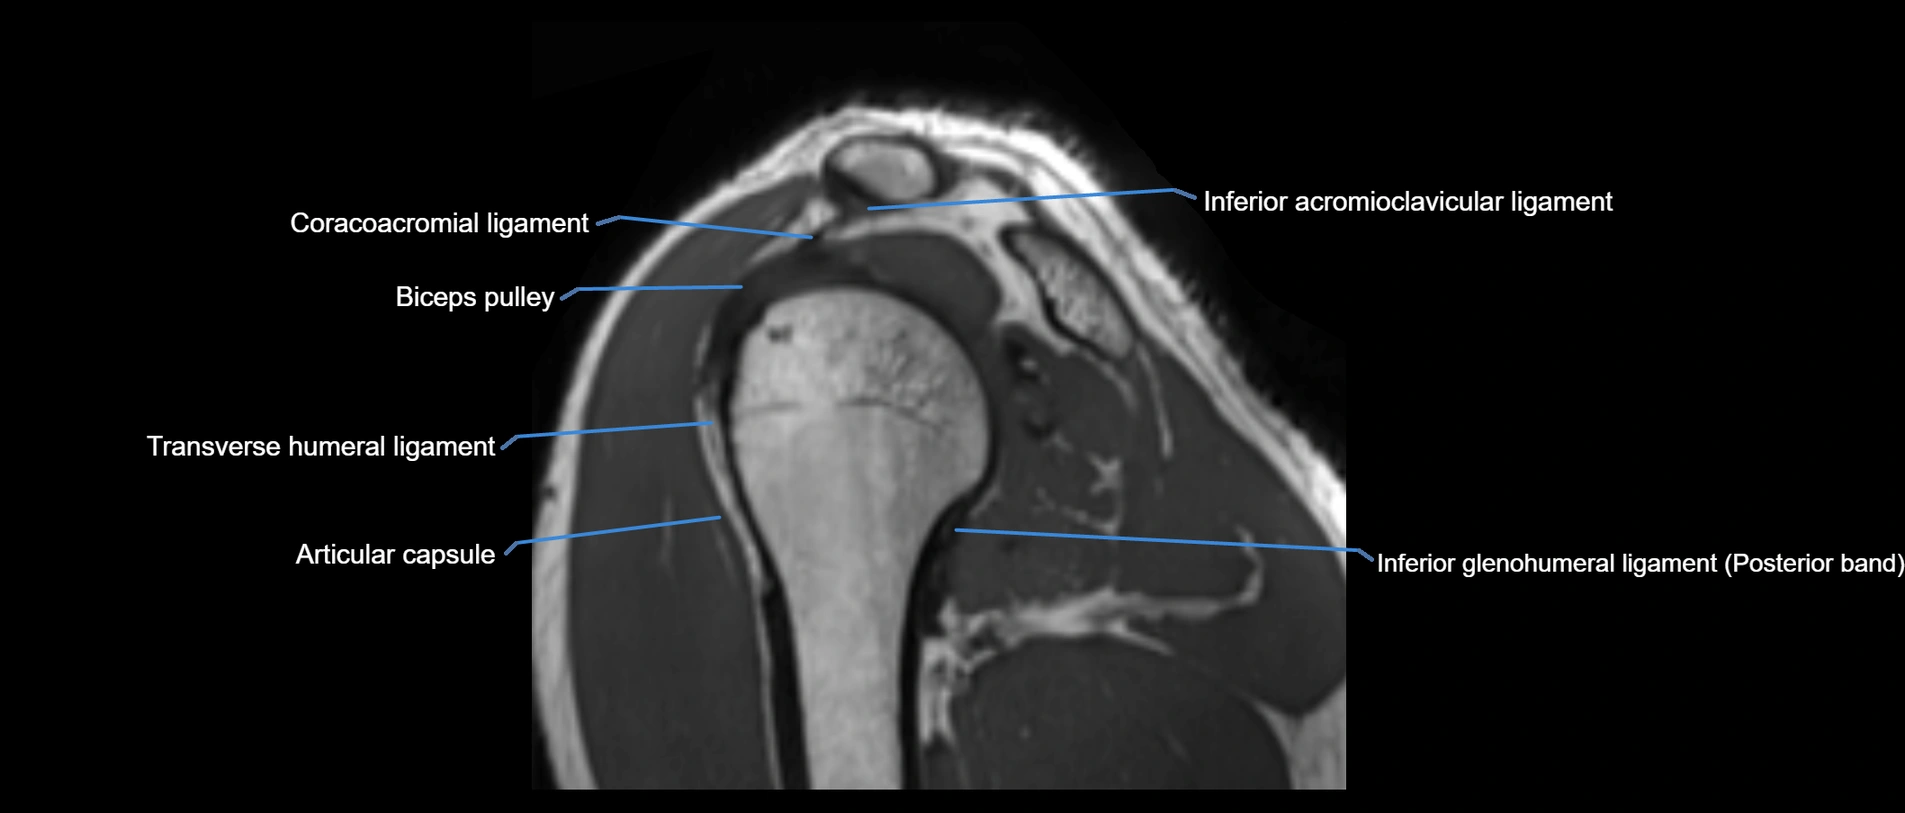

CT image

image